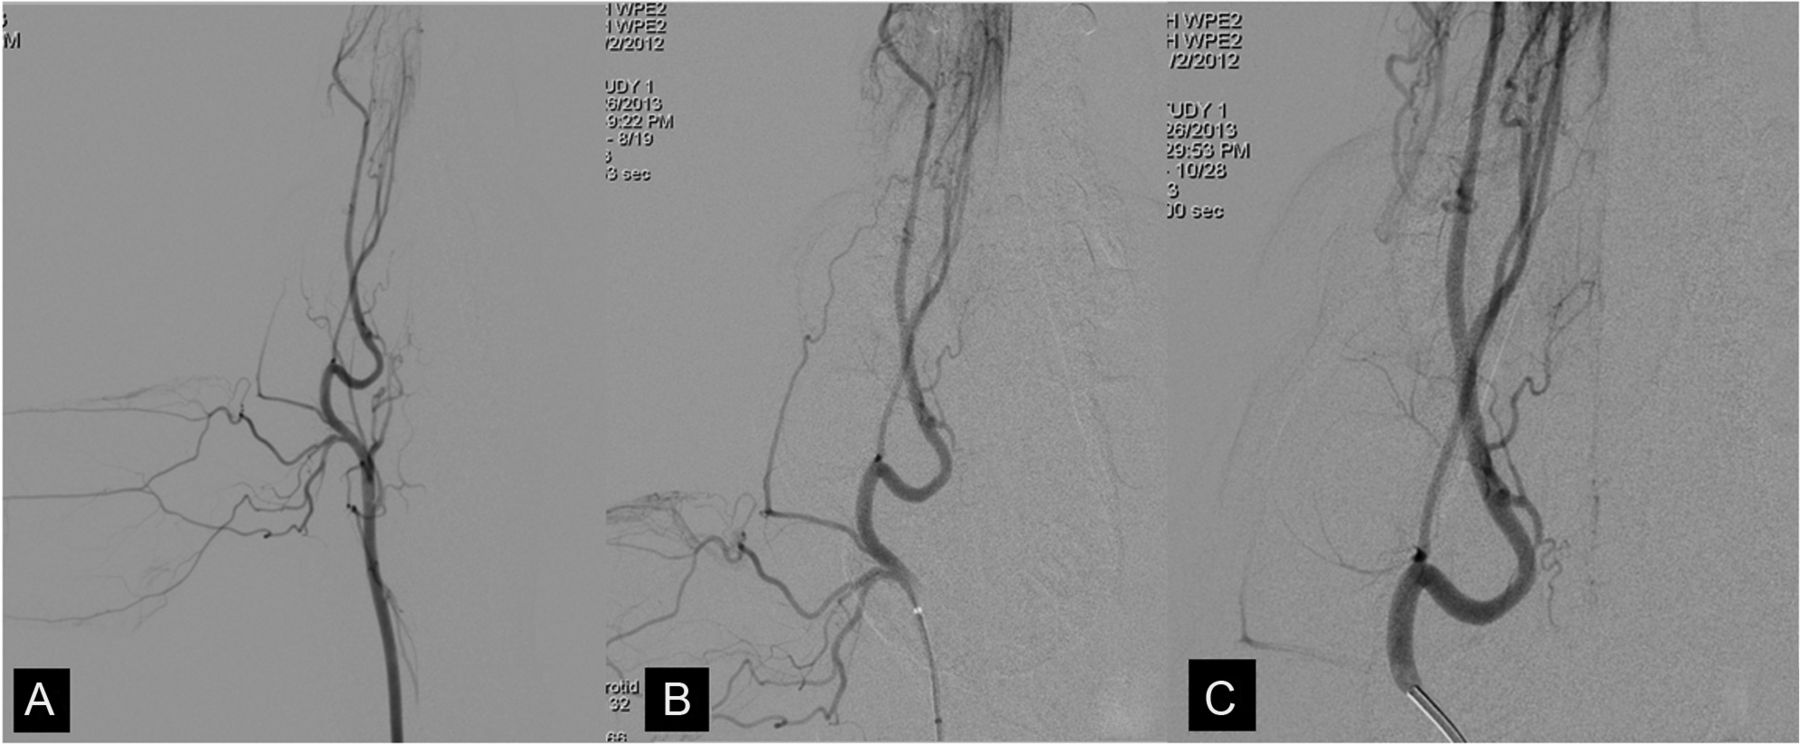

After induction of endotracheal anesthesia, a 4F catheter was introduced into 1 common femoral artery. Under fluoroscopic guidance, the catheter was positioned first in one of the common carotid arteries, then more distally at a location just past the origin of the ICA, and finally still more distally at a location just beyond the superficial temporal artery. This sequence of locations for injections was chosen so that there would be a decrease in the complexity of the vasculature as the injection location was moved more distally. Figure 1 shows an example of these vascular territories on 2D DSA images.

Example of the vasculature on anteroposterior 2D DSA projections for each catheter position: proximal (A), middle (B), and distal (C). These show the decrease in the vascular complexity as the injection site is moved from proximal to most distal. The magnification factor for the images increases, moving from proximal to most distal.